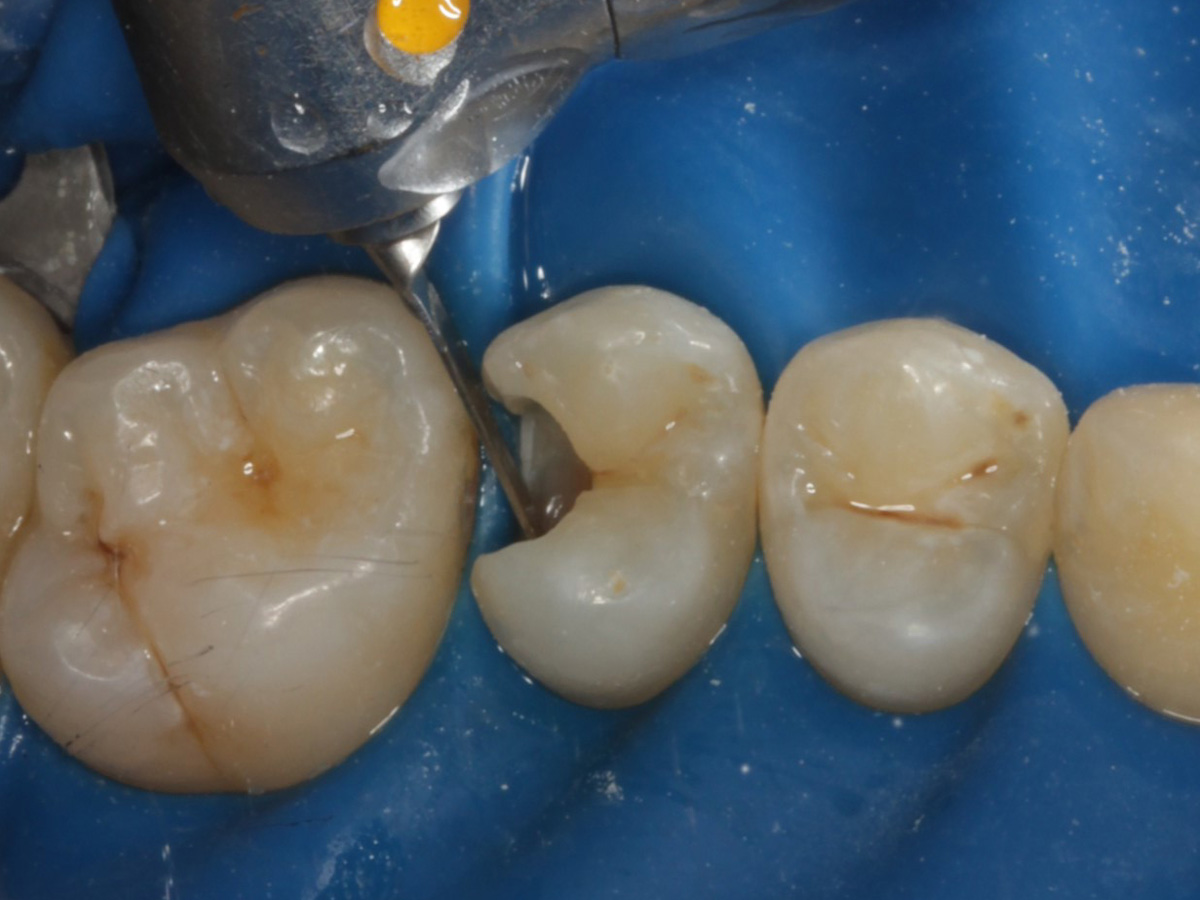

Abbildung 1

Approximalraumkaries an Zahn 25 distal